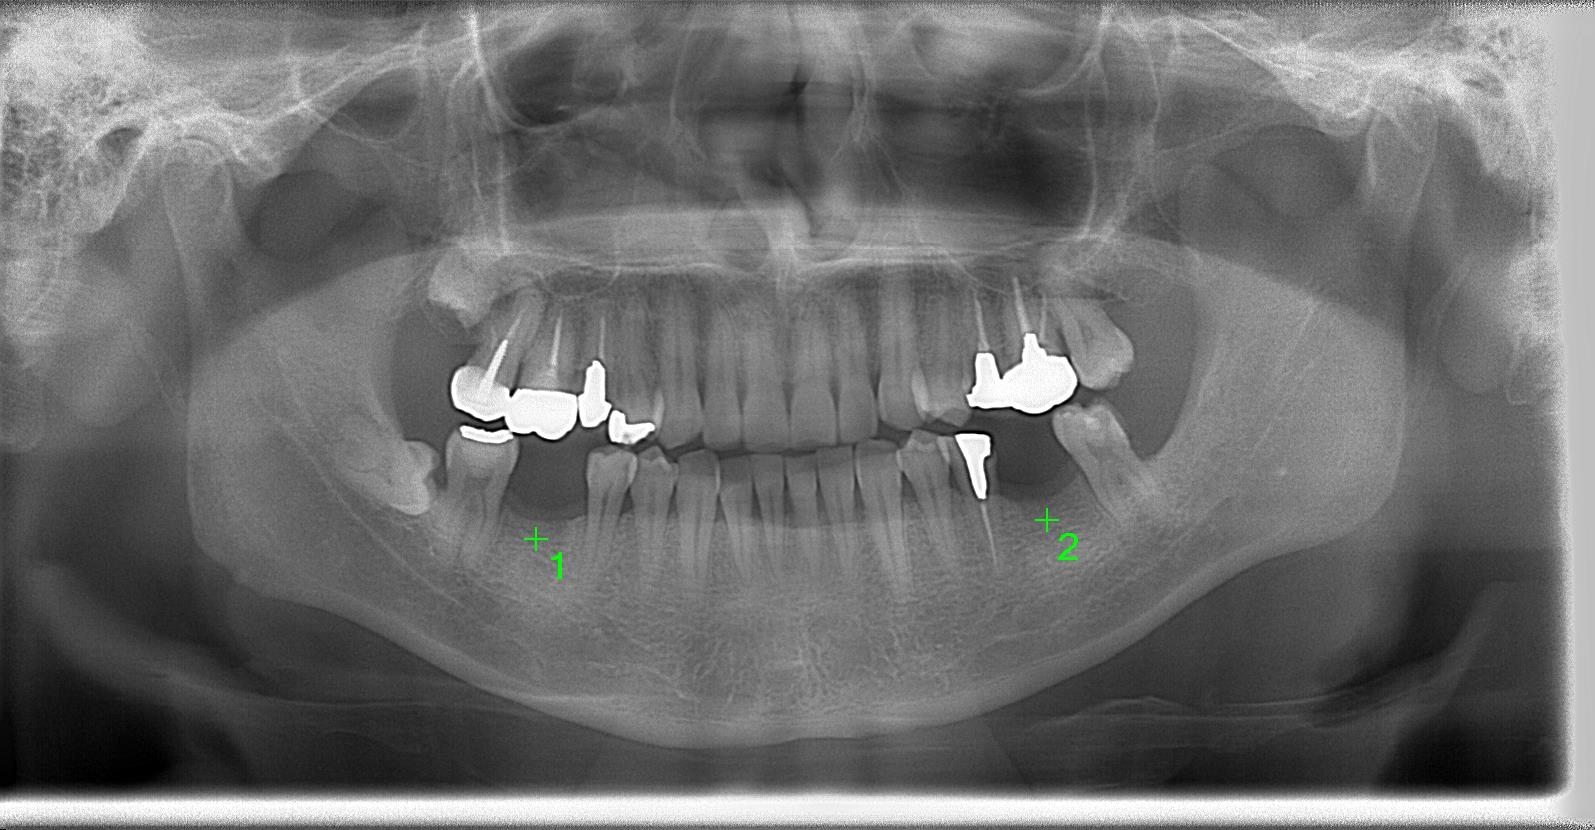

術前パノラマレントゲン写真